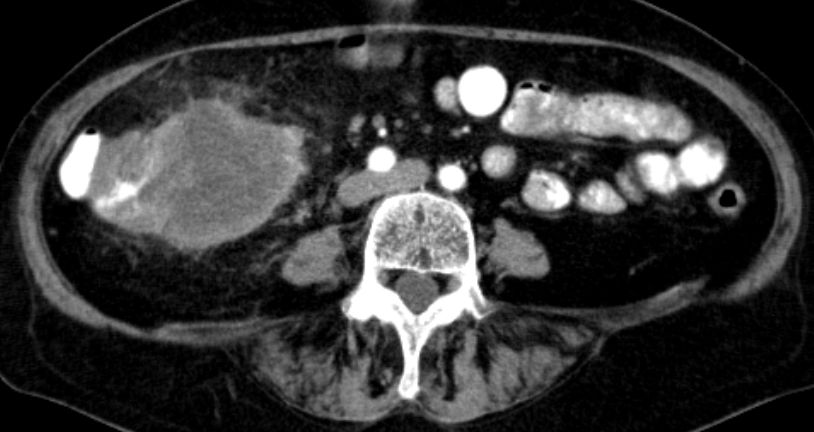

| Colon ascendens | 7-jährige Frau mit Colon ascendes Tumor pT3d pN2a(4/20) L1 Vo.

Großer Tumor mit Infiltration des Fettgewebes. Kein Ileus! |